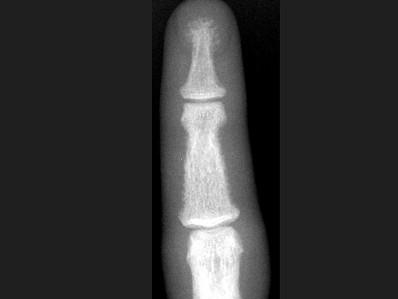

女,41岁,慢性肾功能不全,结合图像,最可能的诊断是?(?)A.白血病B.甲状旁腺功能亢进C.地中海贫血D.镰状细胞贫血E.骨关节结核

问题 女,41岁,慢性肾功能不全,结合图像,最可能的诊断是?(?)

选项 A.白血病 B.甲状旁腺功能亢进 C.地中海贫血 D.镰状细胞贫血 E.骨关节结核

答案 B